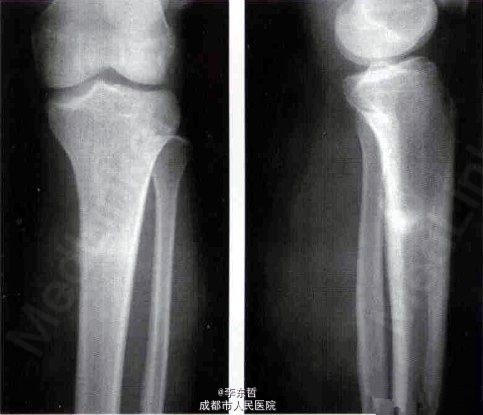

左胫腓骨疲劳性骨折

患者男性,19岁,武警战士,长期专业训练,左小腿疼痛半年余。